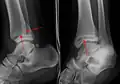

Une fracture triplane de la cheville vue sur une radiographie standard

Radiographie

Vues

Il y a trois vues radiographiques dans une série complète de cheville : antéropostérieure (AP), latérale et oblique (ou "vue de mortaise"). La vue de la mortaise est une radiographie AP prise avec la cheville tournée vers l'intérieur de 15 à 20 degrés puisque le pied est naturellement tourné vers l'extérieur par rapport à la cheville[8].

Sur les radiographies, on peut voir une fracture de la malléole médiale, de la malléole latérale et/ou du bord antéro-postérieur du tibia distal. Le bord postérieur (appelé malléole postérieure) est beaucoup plus fréquemment lésé que la face antérieure du tibia distal. Si les malléoles latérale et médiale sont brisées, on parle de fracture bimalléolaire (certaines d'entre elles sont appelées fractures de Pott (en)). Si la malléole postérieure est également fracturée, on parle de fracture trimalléolaire.[réf. nécessaire]